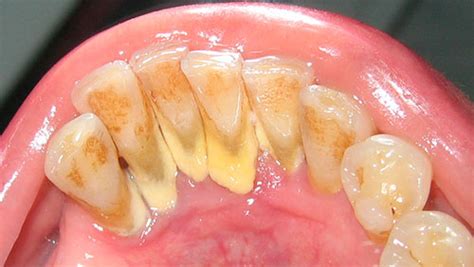

El sarro en los dientes, también conocido como tártaro o cálculo dental, es uno de los problemas orales más comunes. El sarro dental es una capa de suciedad y residuos calcificados que se acumula en los dientes como consecuencia de una higiene oral insuficiente o ineficiente.

El sarro se distingue por su color, que puede ir de blanquecino a pardo. Además los problemas estéticos derivados de su aspecto desagradable, su presencia puede traer consecuencias negativas para la salud oral.Esta capa de suciedad también se puede amontonar en el borde o debajo de las encías, llegando a irritar los tejidos gingivales. El sarro está colonizado por las bacterias de la cavidad oral o placa bacteriana, responsable a su vez de muchas de las patologías de los dientes y encías.